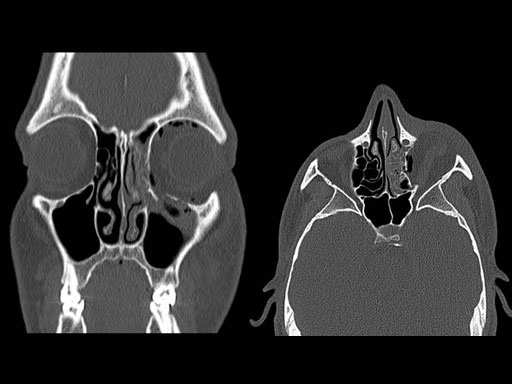

30 year old male patient with fracture of left orbital floor and medial wall.

Provided by Dr Dr Marc C Metzger, Freiburg, Germany.